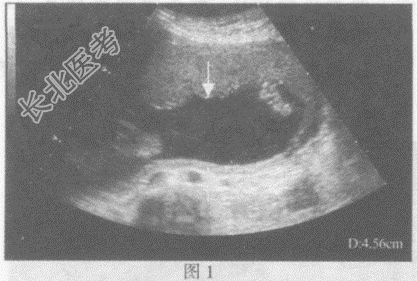

- 单项选择题请指出下图箭头间所指的是宫内妊娠哪个部位:

A、图1:胎盘厚度,图2:羊水深度

B、图1:羊水深度,图2:胎盘厚度

C、图1:胎儿双顶径,图2:胎儿腹围

D、图1:胎儿股骨长径,图2:胎儿股骨长径

E、图1:胎儿腹围,图2:胎儿双顶径